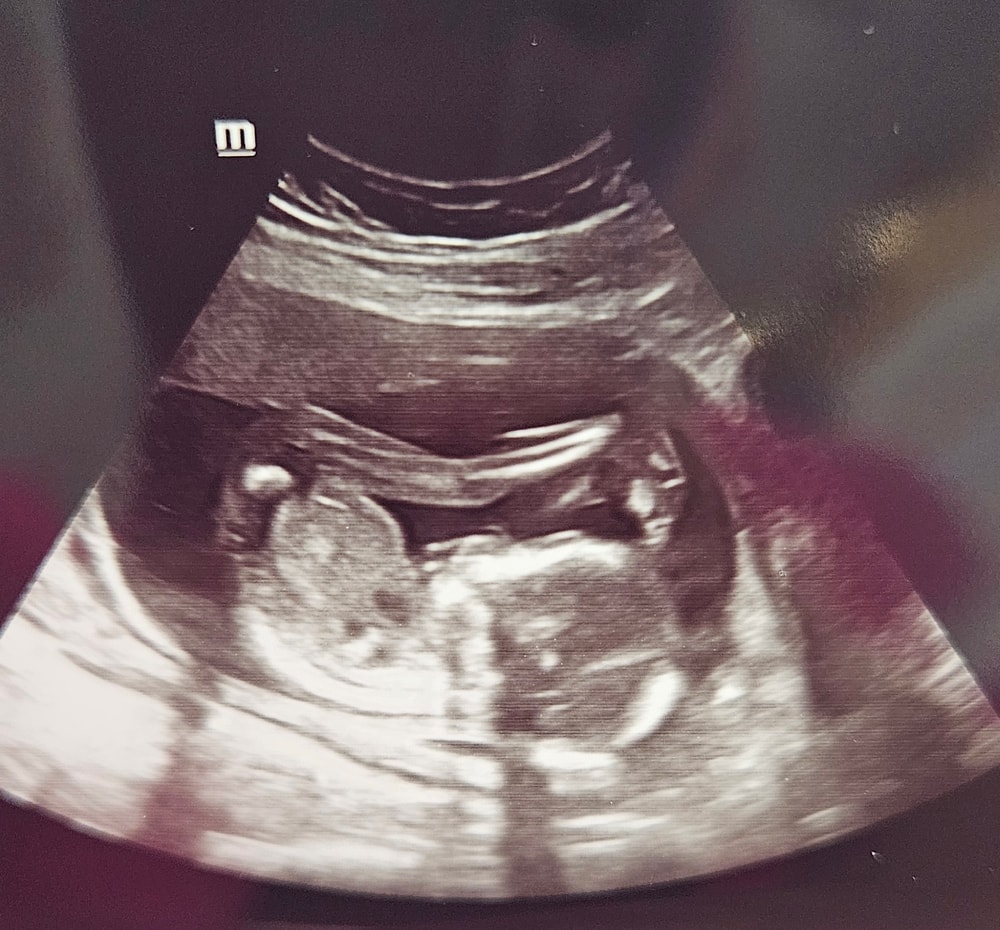

А нам сегодня 17 недель💙❤️

Всё о нашей беременностиСходила на межскрининговое узи)

Сын, почти 200гр

Рост 22 см)

Мой акробатик ростёт, такой подвижный, ножки задрал))) по всякому от мамы так отталкивался, забавно🥹🥹🥹 с узи вышла вся окрыленная) 🙏🙏🙏